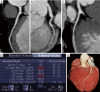

Example of FFRCT in a normal left anterior descending artery (LAD). A 55-year-old man with hypertension and atypical chest pain. (A) Normal LAD; (B) FFRCT three-dimensional model with different coronary segments FFRCT values (Software FFRct prototype by SIEMENS Frontier).

FFRCT in a diseased left anterior descending artery (LAD). A 73-year-old female with family history of cardiac heart disease, diabetes (insuline), dislipidemia, hypertension (under treatment) and typical effort angina. (A) A coronary calcified plaque in LAD, (B) an FFRCT value of 0.857872 (SmartFFR, SMARTool platform for clinical decision support system-CDSS).